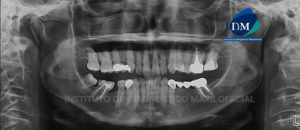

Paciente de sexo femenino de 53 años de edad, acude al Instituto de Diagnóstico Maxilofacial (Sede Miraflores) por dolor a nivel de la pieza 17.